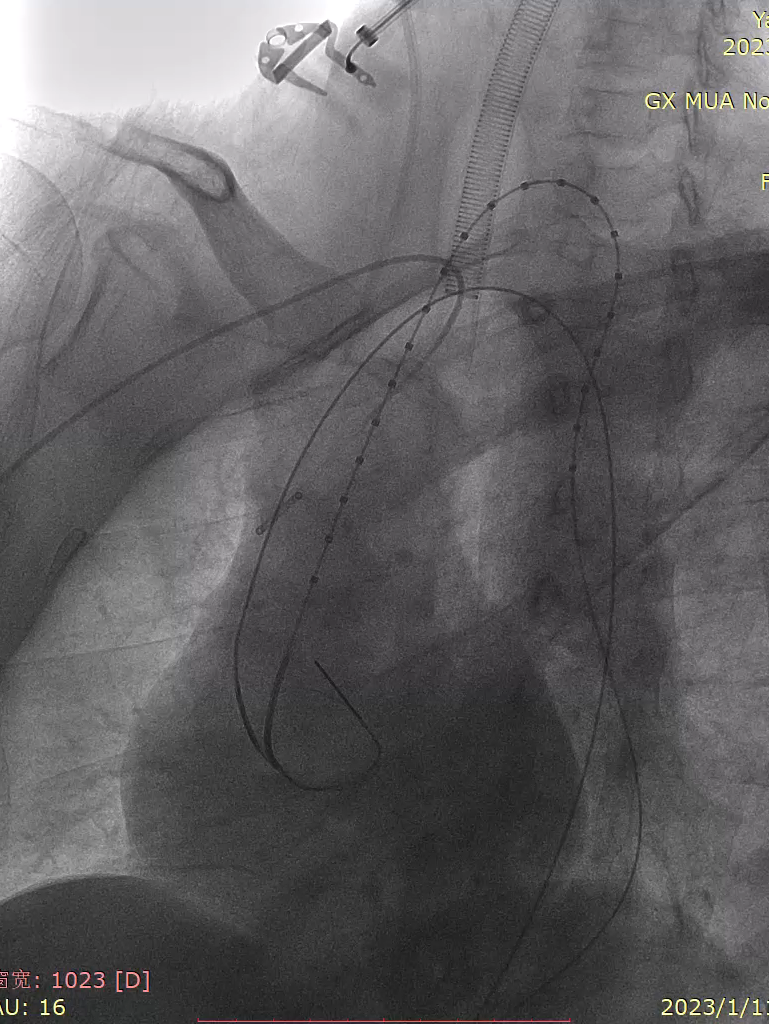

推送主体于目标锚定区更前端定位造影

支架输送系统塑型至弓部导丝支撑完成支架输送前置于LCCA前,将引导鞘退至降主。

gore医疗怎么样「胸有乾坤」化险为夷,通险畅机——GORE® TAG® 胸主动脉覆膜支架治疗累及异形弓部动脉瘤_https://www.jmylbn.com_新闻资讯_第17张

造影明确定位并将支架后移至左颈开口后缘标记定位点。

gore医疗怎么样「胸有乾坤」化险为夷,通险畅机——GORE® TAG® 胸主动脉覆膜支架治疗累及异形弓部动脉瘤_https://www.jmylbn.com_新闻资讯_第19张

远端接主体

第一支架释放完毕后造影可见:LCCA显影良好,支架近端完全贴壁无鸟嘴。

远端LSA显影和Ib型漏,故在在第一支架内接入同型号第二支架,内漏消失,LSA显影延迟。

gore医疗怎么样「胸有乾坤」化险为夷,通险畅机——GORE® TAG® 胸主动脉覆膜支架治疗累及异形弓部动脉瘤_https://www.jmylbn.com_新闻资讯_第22张

第一支架远端存在Ib型漏

gore医疗怎么样「胸有乾坤」化险为夷,通险畅机——GORE® TAG® 胸主动脉覆膜支架治疗累及异形弓部动脉瘤_https://www.jmylbn.com_新闻资讯_第23张

补充第二支架

gore医疗怎么样「胸有乾坤」化险为夷,通险畅机——GORE® TAG® 胸主动脉覆膜支架治疗累及异形弓部动脉瘤_https://www.jmylbn.com_新闻资讯_第24张

最终造影

术后复查

复查造影可见胸主动脉显影良好,支架在位无鸟嘴,支架内显影良好无内漏,瘤腔造影剂无明显外溢,右头臂动脉,左颈总动脉显影良好,患者声嘶症状即刻减轻,但仍能触及颈部包块轻微搏动,考虑为LSA返流所致。